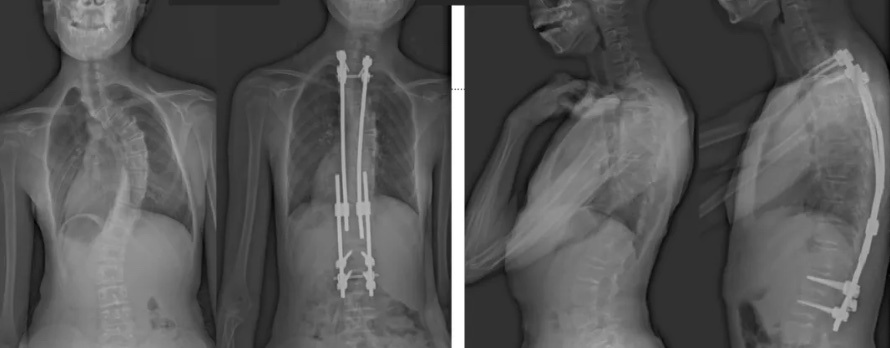

白瑪的正位術前、術后對比圖(左側);側位術前、術后對比圖(右側)